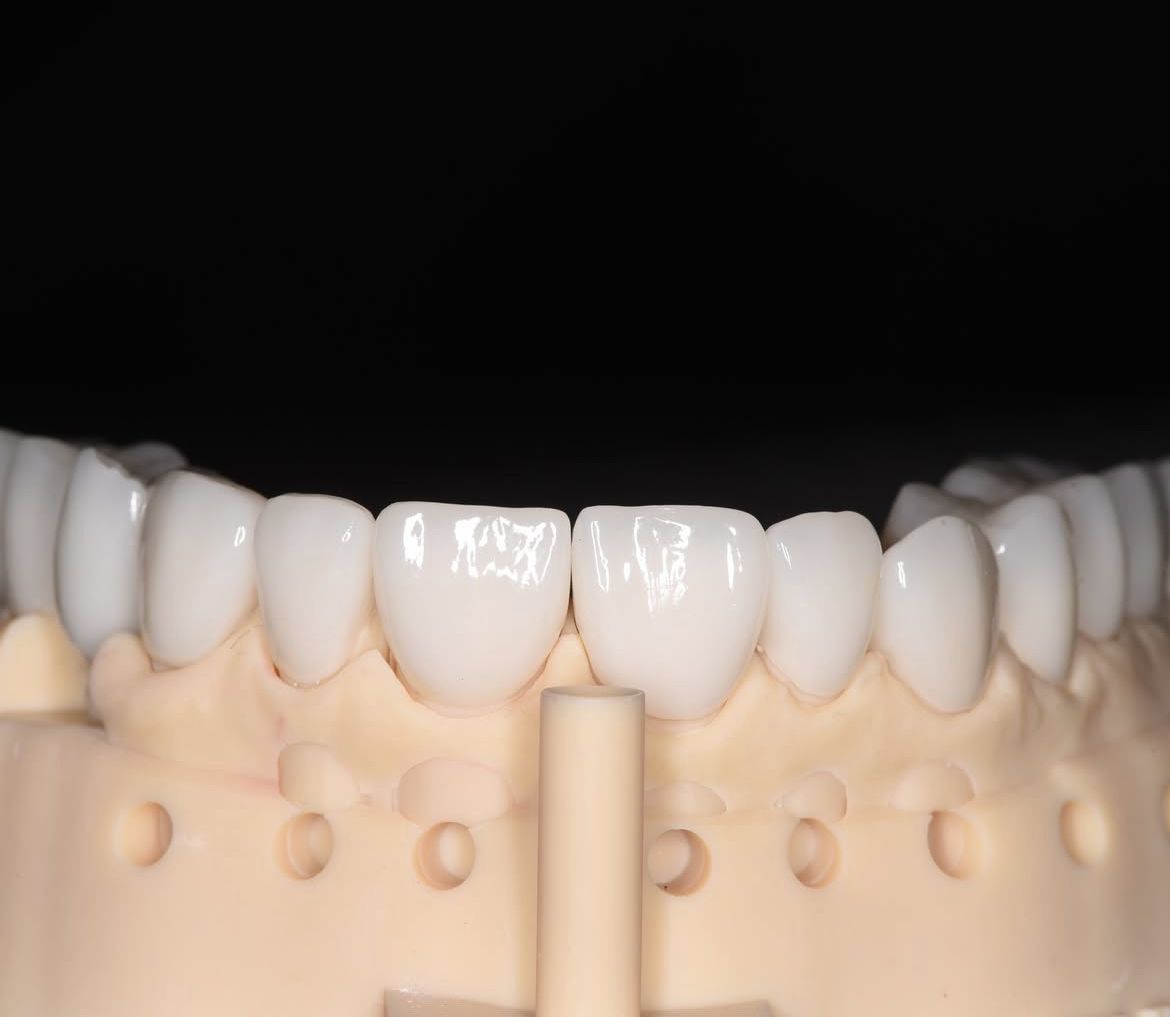

- protetyka (korony ceramiczne (cerkon, E-max), licówki, mosty, protezy ruchome, korony na teleskopach, inlay, onlay, overlay, endkorony);